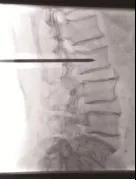

手術(shù)中情況

4月21日,我院骨科孫守全專家小組為老人進(jìn)行了PKP手術(shù),術(shù)后當(dāng)天老人腰背部疼痛銳減,己能坐起吃飯。術(shù)后第二天就能下床大小便,生活已能基本自理。七天后,老人順利出院!按照常規(guī)治療方法,需臥床三個(gè)月,還有可能出現(xiàn)尿路感染、肺部感染等等一系列并發(fā)癥。這結(jié)果與現(xiàn)在相比真有天壤之別!據(jù)了解,PKP手術(shù)為脊椎的微創(chuàng)手術(shù),手術(shù)時(shí)間短、創(chuàng)傷小,出血少,止痛效果明確,恢復(fù)比較快。尤其是對(duì)于高齡衰弱的患者而言,采用PKP手術(shù)治療,患者承擔(dān)的手術(shù)風(fēng)險(xiǎn)極大地減少,并且避免了長(zhǎng)期臥床所導(dǎo)致的潛在并發(fā)癥。但該手術(shù)部位鄰近脊柱總神經(jīng),需要施術(shù)者嫻熟的手術(shù)技巧和細(xì)心大膽的手術(shù)操作。我院骨科在濰坊市較早引入椎體成形術(shù),目前已經(jīng)為近千名老人解除了"腰痛"病痛。